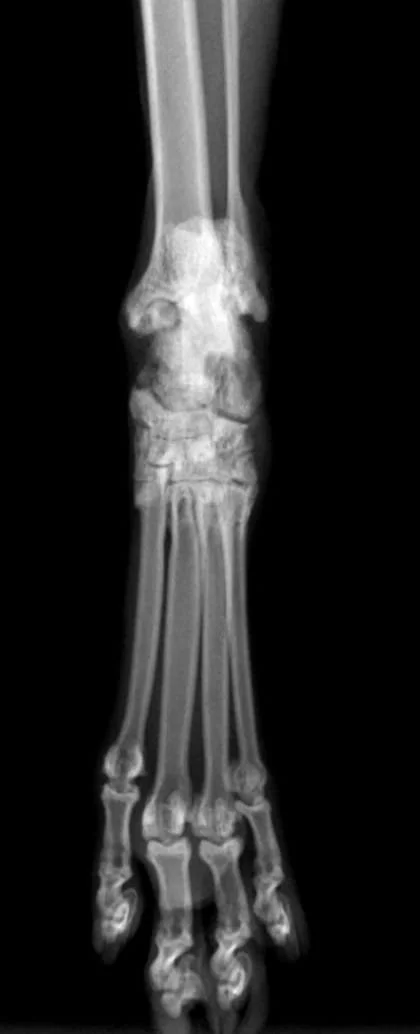

Orthopedic radiographs and genetic testing was performed with sedated patient, which confirmed diagnosis of Osteochondrodiplasia.

radiological finding consisted in irregularity in shape of tarsal and metatarsal bones, narrow tarsal joint spaces, and mild new bone formation around tarsal joints.